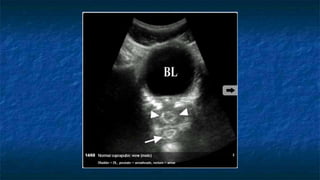

3)FAST: Pelvis exam

 Pelvis: Longitudinally and Transvers Axis.

 Probe placed

 Transeversally then Longitudinally

 Midline 2 cm superior to the symphysis pubis

 “aimed” caudally into the pelvis (prostate )

 Probe facing

 Toward patient’s head and right side.

 Best with some urine in bladder(acoustic window)

 Evaluating

 Bladder ,Uterus in female ,and Prostate in

male

 The potential spaces are Pouch of

Douglas (Cul de sac ) in female and

retrovesicle space in male

FAST: Pelvis exam

 Pelvis: Transverse Axis

 Normal Anatomy

 Evaluating Bladder

 Well cirucumscribed

 Contains fluid that

appears anechoic

Transverse